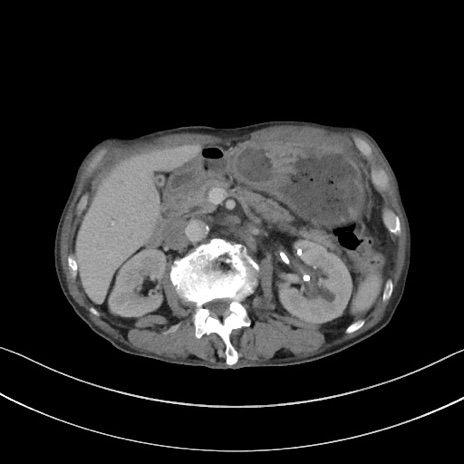

症例3(横断像)

【症例】 70歳代男性

【主訴】右鼠径部腫瘤、疼痛

【現病歴】本日朝より上記主訴あり、受診。

【既往歴】膀胱癌にて膀胱全摘、両側尿管皮膚瘻

【データ】WBC 5600、CRP 0.56